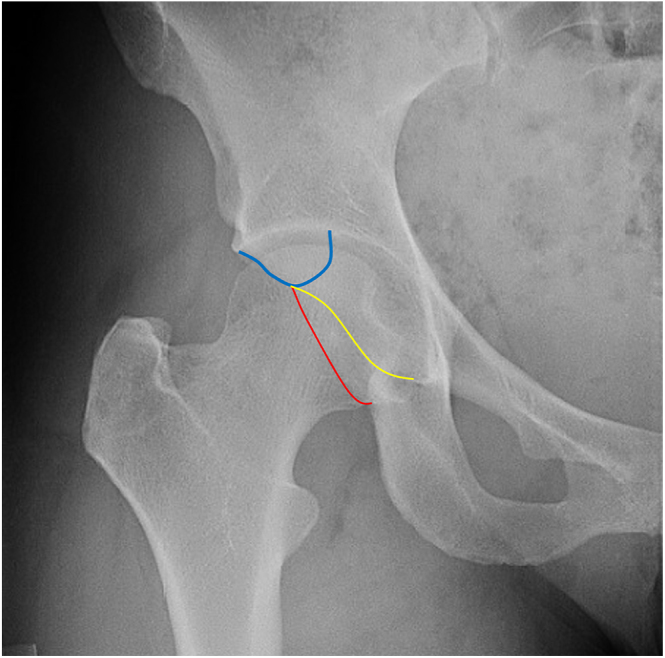

髋关节疼痛可由关节外情况引起,如脊柱下撞击、髂腰肌撞击和坐骨股撞击。这些综合征通常继发于髋关节或腰椎的潜在病变。虽然大多数病例通过活动调节和物理治疗进行保守治疗,但对难治性病例考虑手术干预。计算机断层扫描(CT)和磁共振成像(MRI)等成像对于诊断这些疾病至关重要,因为临床症状可能是非特异性的。CT扫描有助于确定诱发因素,如髋臼形态、股骨变形和髋臼变形,而MRI有助于排除其他情况和检测软组织病理。虽然通常观察到积极的治疗结果,但结果和程序存在差异,并且缺乏长期随访研究。治疗的并发症是一个问题,但大多数报道的并发症是轻微的性质。

Hip pain can be caused by extra-articular conditions such as subspine impingement, iliopsoas impingement, and ischiofemoral impingement. These syndromes are frequently secondary to underlying pathologies involving the hip joint or lumbar spine. While most cases are managed conservatively through activity modification and physiotherapy, surgical intervention is considered for refractory cases. Imaging, such as computed tomography (CT) scans and magnetic resonance imaging (MRI) is crucial for diagnosing these conditions, as clinical symptoms can be nonspecific. CT scans help identify predisposing factors such as acetabular morphology, femoral version, and acetabular version, while MRI is useful for ruling out other conditions and detecting soft tissue pathology. Although positive treatment outcomes are generally observed, there are variations in results and procedures, and long-term follow-up studies are lacking. Complications of the treatments are a concern, but most reported complications are minor in nature.